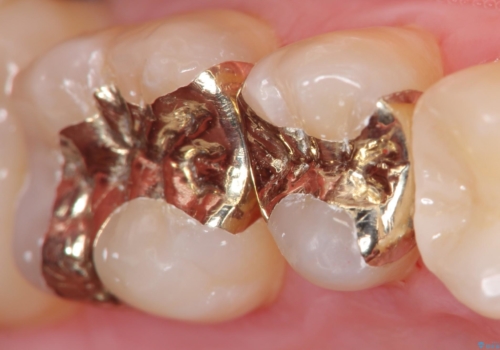

- 12万円 ゴールドインレー×2費用は治療当時の料金となります

ゴールドインレーについて

ゴールドは見た目に難がありますが、歯を削る量がセラミックに比べて少ない・複雑な形にも追従しやすい・壊れにくいなどの利点があります。